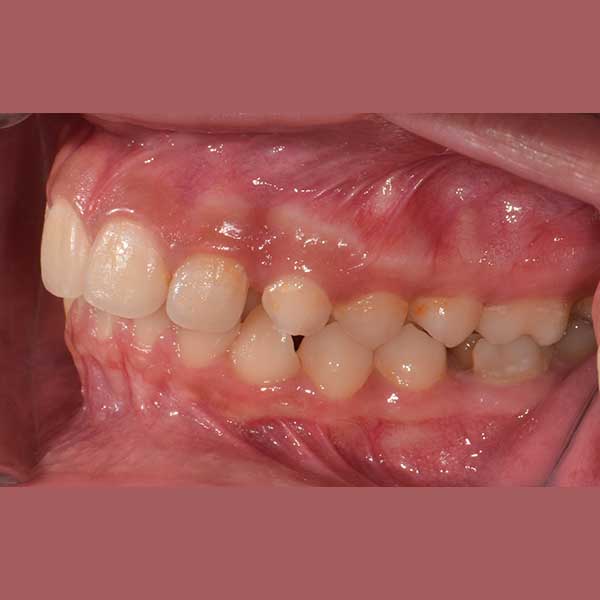

This young woman was suffering from overlapping of her teeth and a lack of sufficient distance of her upper left canine to settle in its natural place, which led to it remaining prominent and higher than the rest of the upper teeth, in addition to the overlapping of her lower teeth greatly, which leads to her inability to clean her teeth well and sedimentation Tartar layers quickly and continuously on these teeth from the back.

By examining the case, it became clear to me that the treatment can be carried out without tooth extraction, through the daemon orthodontic (self-straightening tie), which facilitates the process of expanding the jaws and solving the problem of overlapping.